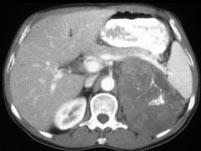

问题 女,43岁,满月脸、皮肤紫纹、月经不规则3个月余,请结合所提供图像,作出诊断 ( )

选项 A、左肾上腺腺癌 B、左肾上腺增生 C、左肾上腺嗜铬细胞瘤 D、左肾上腺转移瘤 E、左肾上腺腺瘤

答案 A